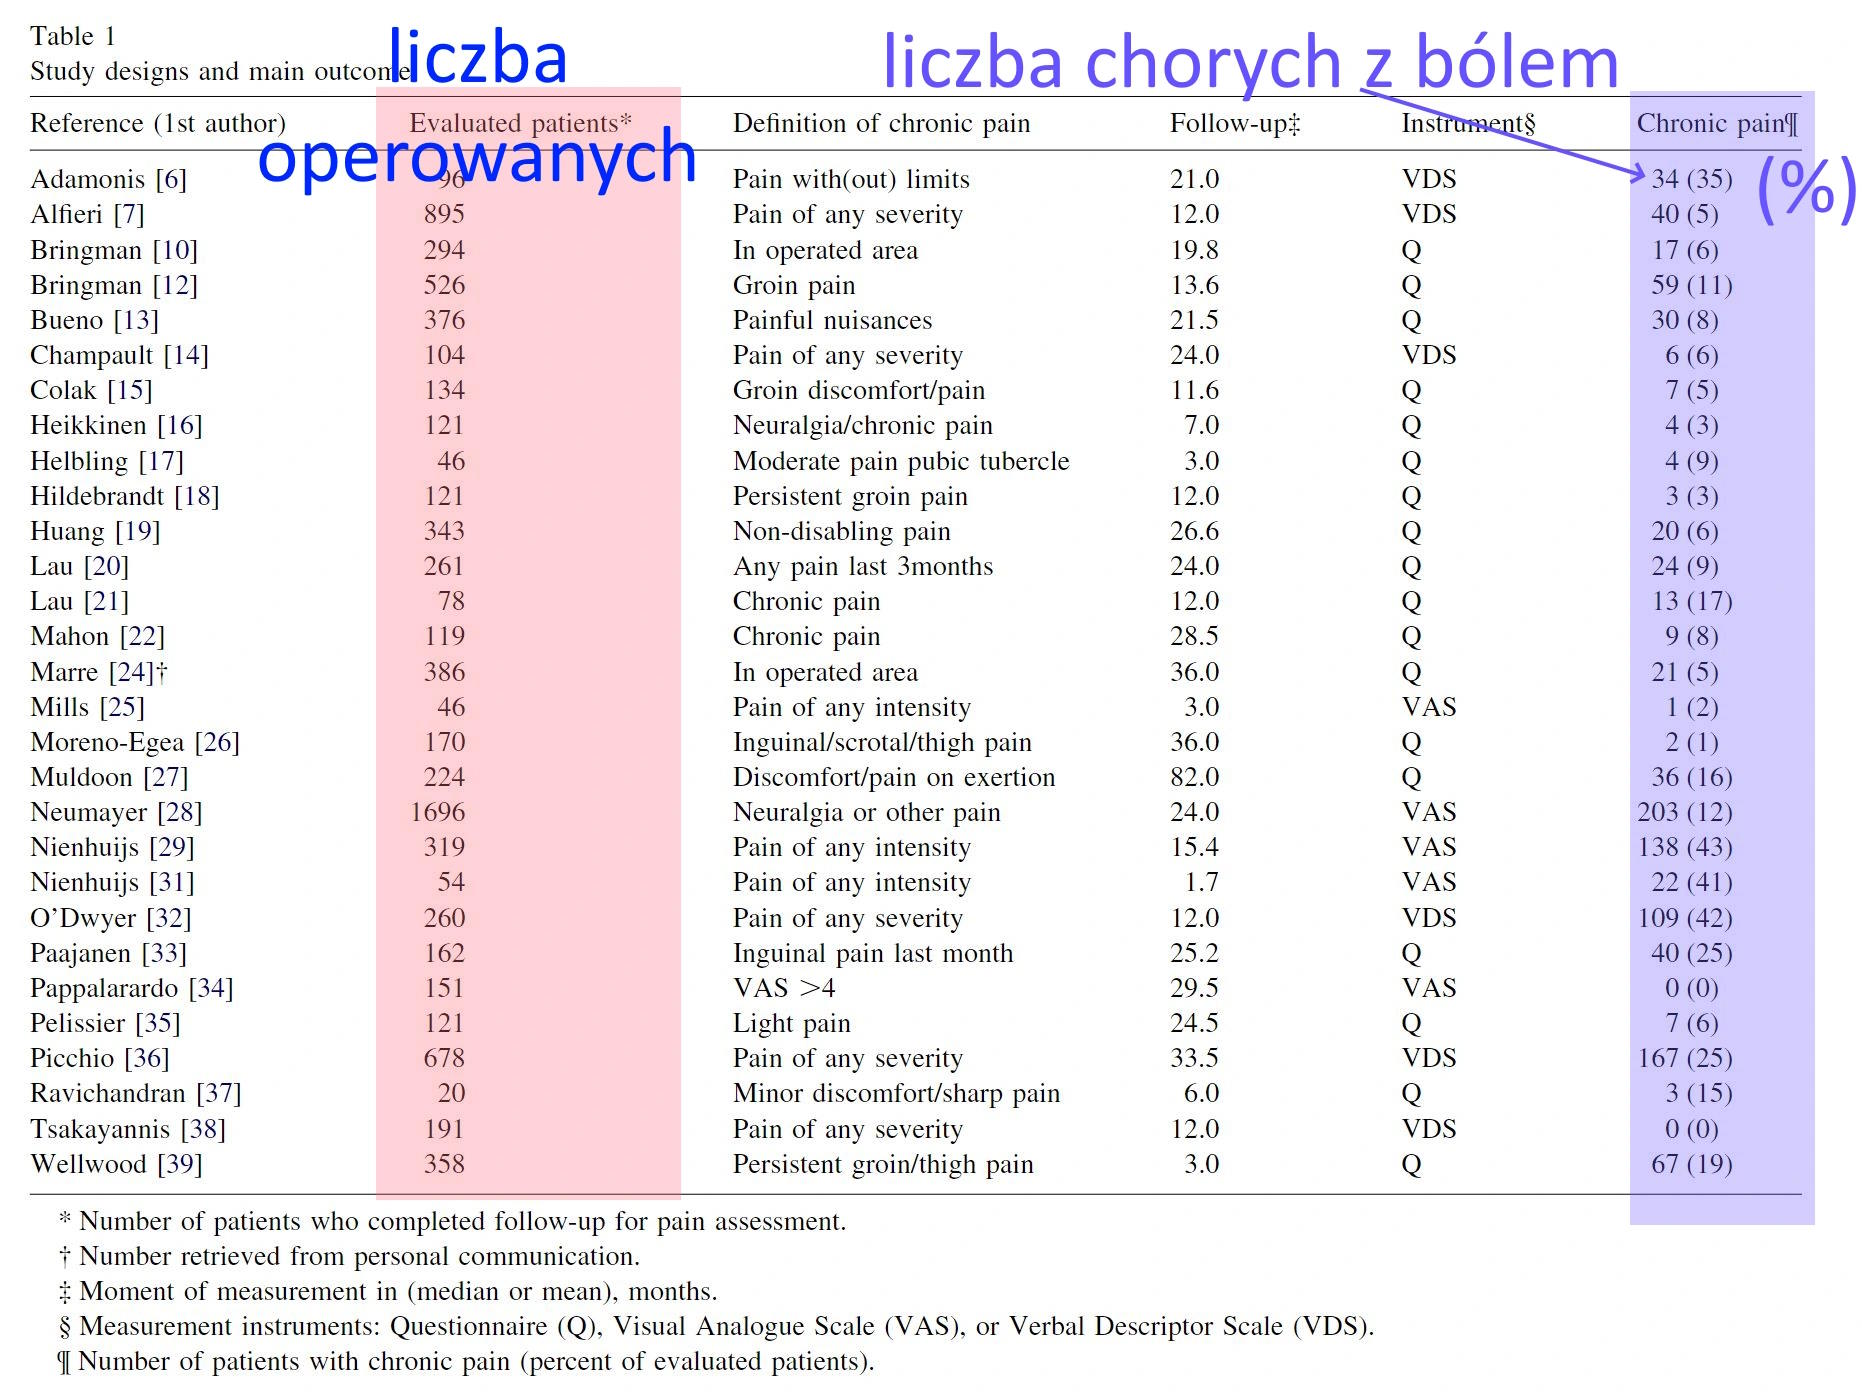

Tu zestawienie zbiorcze wielu prac poświęconych ocenie częstości bólu pooperacyjnego. Po prawej stronie w nawiasach podany jest procent chorych z bólem; skrajne watości to 0 (nikt nie odczuwał bólu) do 42% – prawie co druga osoba po operacji odczuwała ból. Wyniki badaczy znacznie się różnią – ale na pewno problem istnieje.

Wg innych zbiorczych podsumowań częstość występowania przewlekłego bólu po operacji przepukliny wynosi od 11,2% do 50%. Szacuje się, że po 2 do 3 lat po operacji przepukliny bólu nadal utrzymuje się u około 16% operowanych – czyli co 6. osoby.

Wg innych zbiorczych podsumowań częstość występowania przewlekłego bólu po operacji przepukliny wynosi od 11,2% do 50%. Szacuje się, że po 2 do 3 lat po operacji przepukliny bólu nadal utrzymuje się u około 16% operowanych – czyli co 6. osoby.